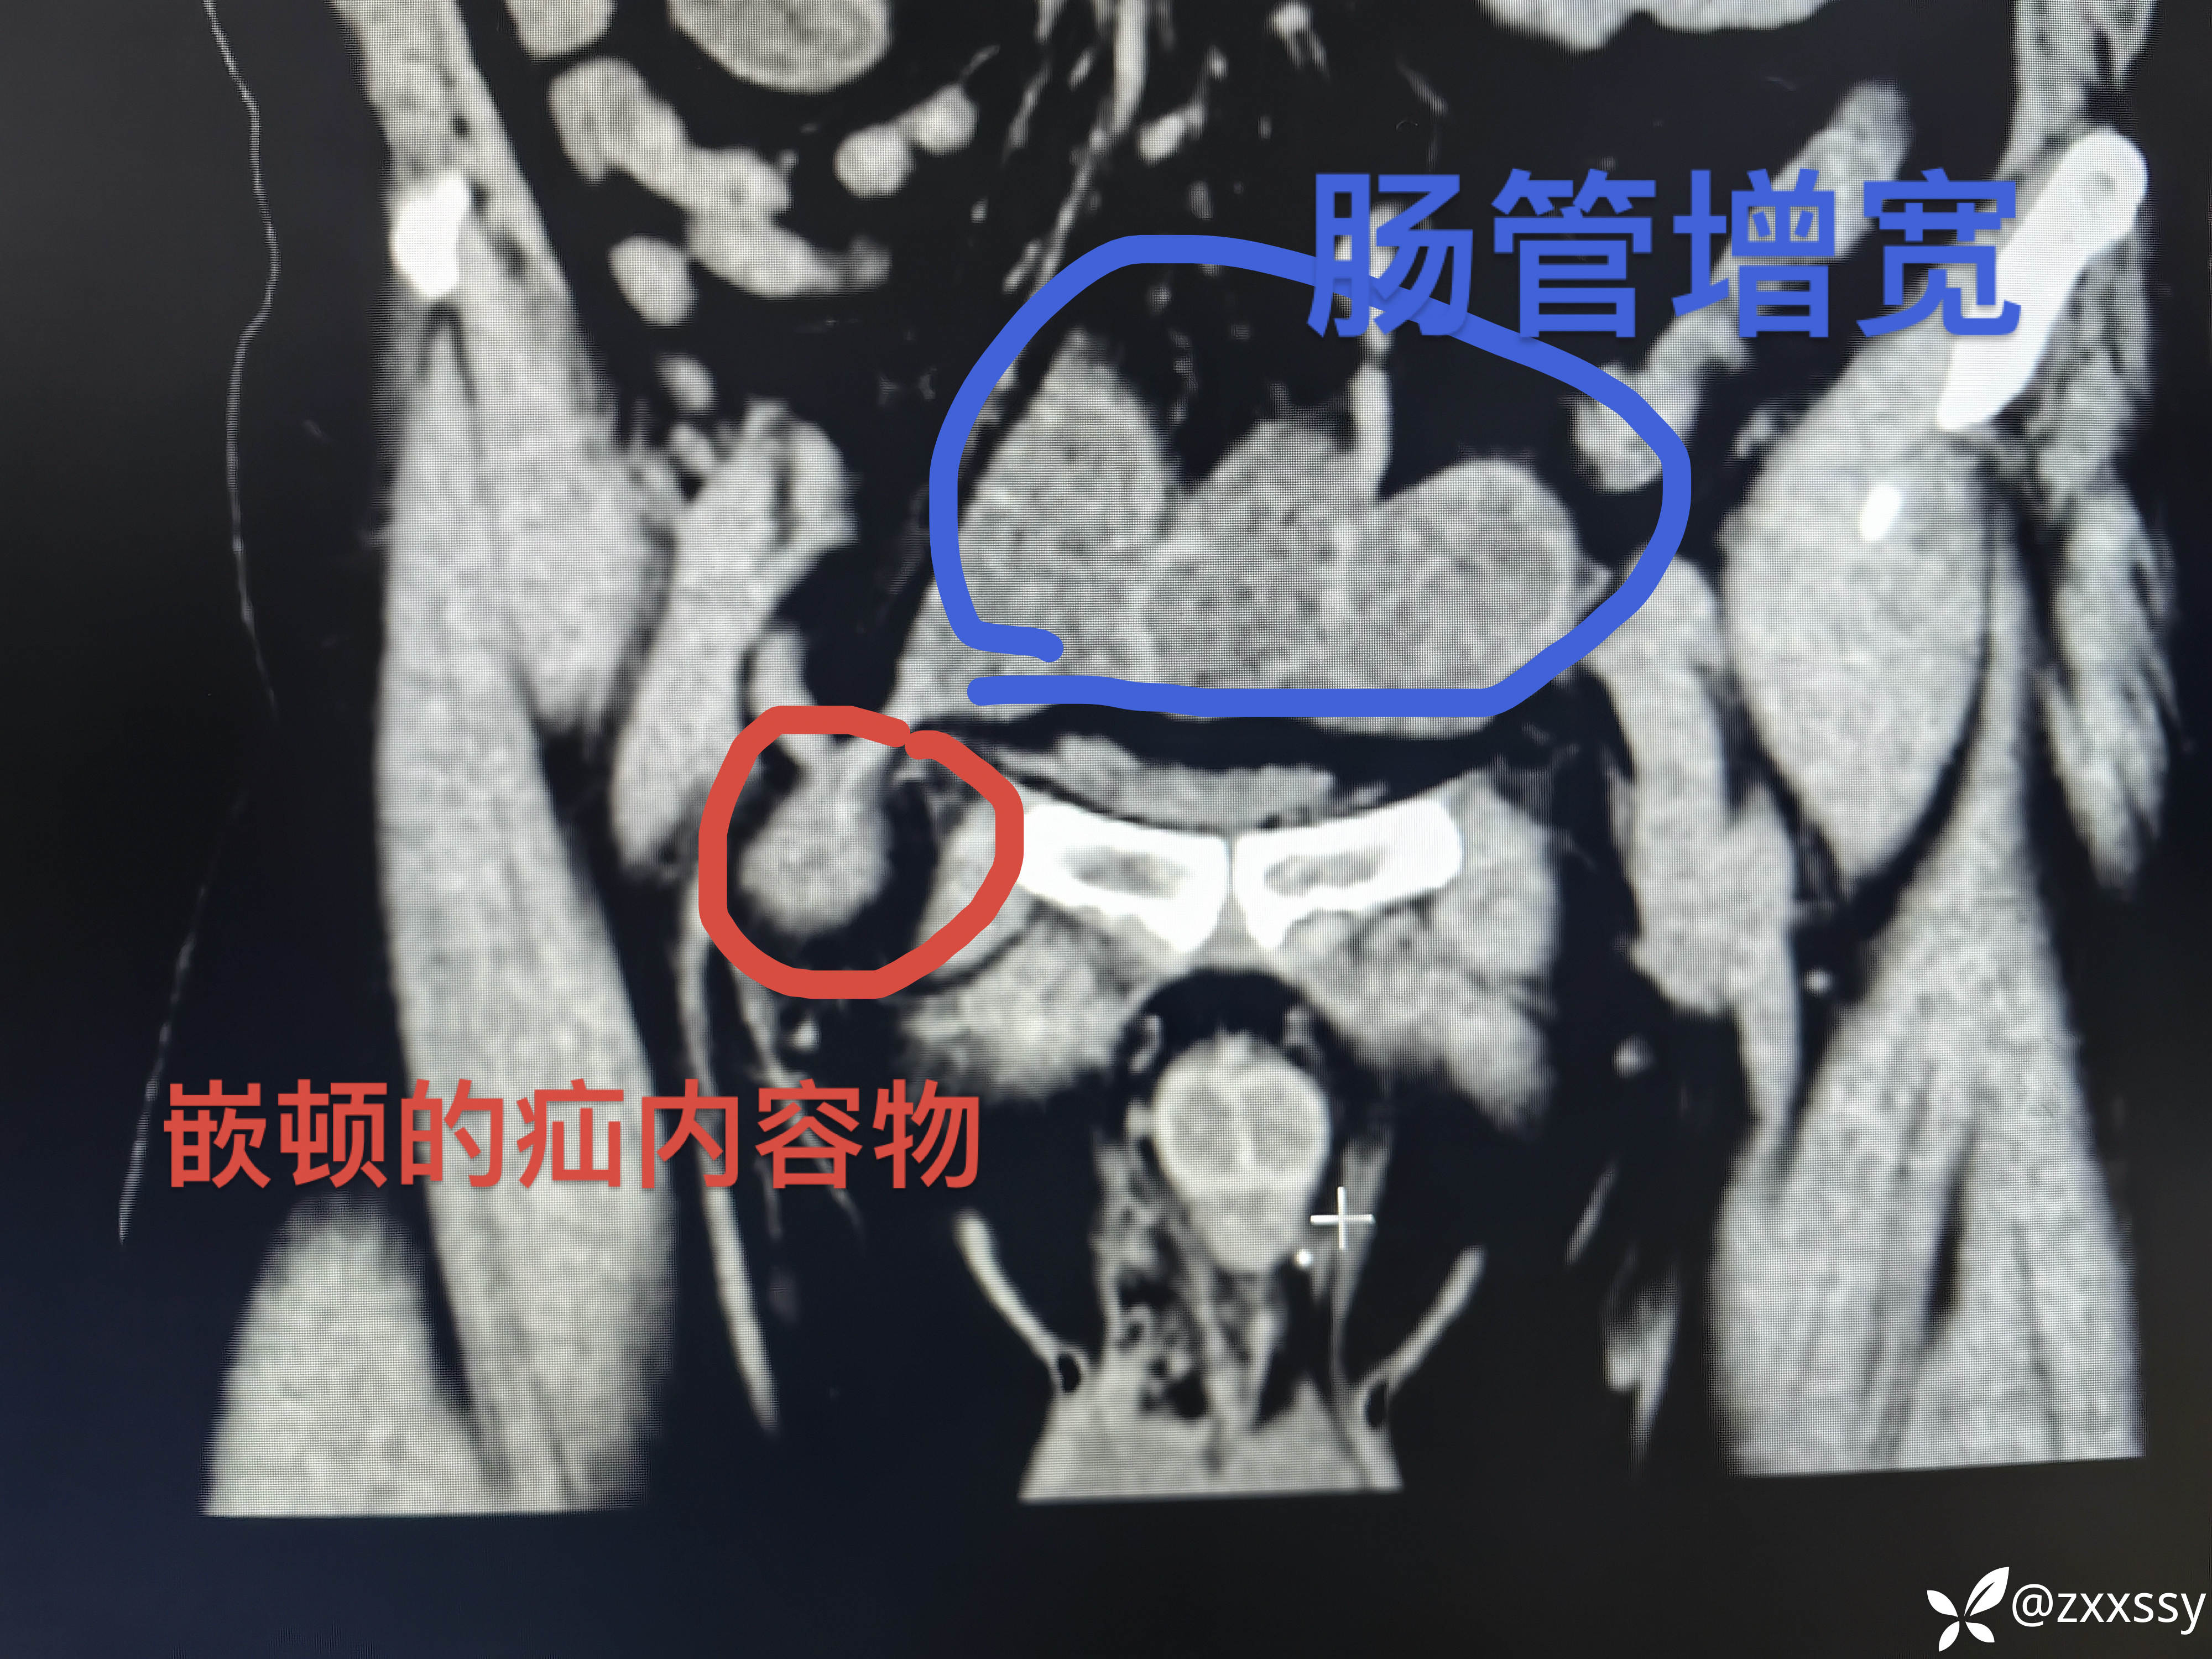

CT:嵌顿的疝内容物明显;肠管增宽、周围渗出:肠梗阻。

【临床诊断】:右侧腹股沟嵌顿疝